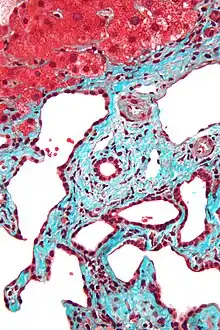

Histopathology of a bile duct hamartoma, low magnification, H&E stain, showing a well demarcated lesion.